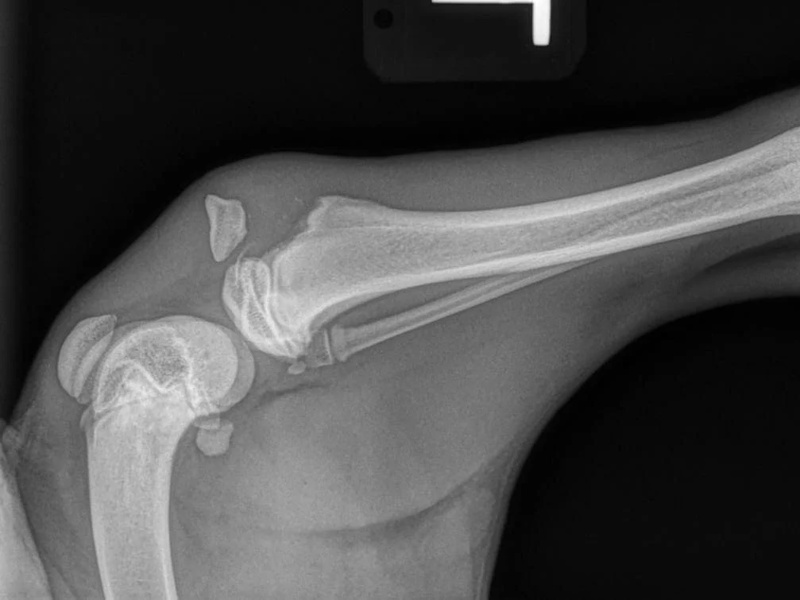

Shoulder Osteochondritis Dissecans (OCD)

How Is Shoulder OCD Treated?

- Surgical Removal of the Cartilage Flap

- SynaCart

Shoulder Osteochondritis Dissecans (OCD) with a SynaCart Implant